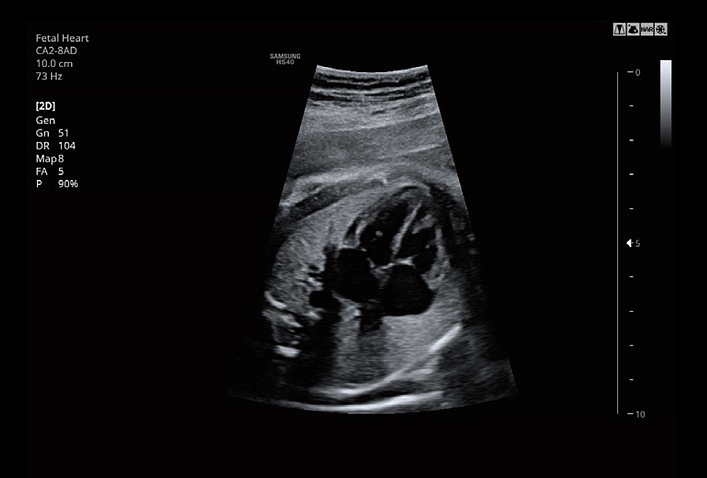

5D NT™ provides the midsagittal plane view automatically by rotating and magnifying the images when measuring the nuchal translucency (NT) of the fetus in early weeks.